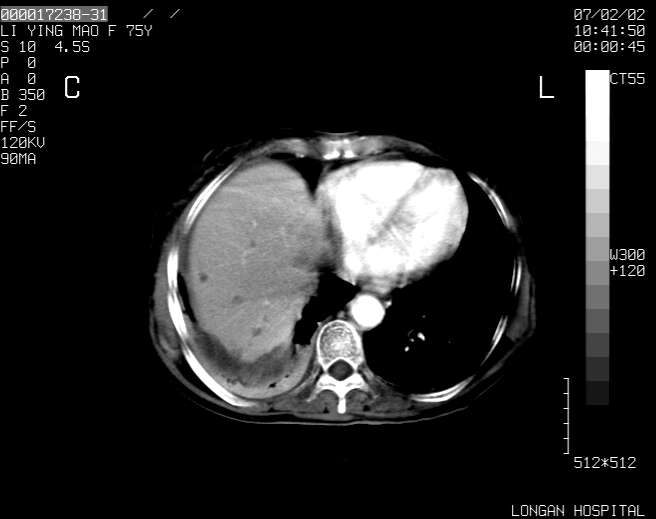

以下是引用dyqct在2007-2-10 8:53:00的发言:[br]考虑:1、肝脏多发囊肿[br] 2、左肾囊肿,右肾多发结石并积水。[br] 3、右胸少量积液。[br] 4、右肾周包裹性积液或淋巴管瘤(有见缝就钻的征象、薄隔、小结节状钙化)?[br] 5、腰椎动脉瘤样骨囊肿?[br] [br] [br]